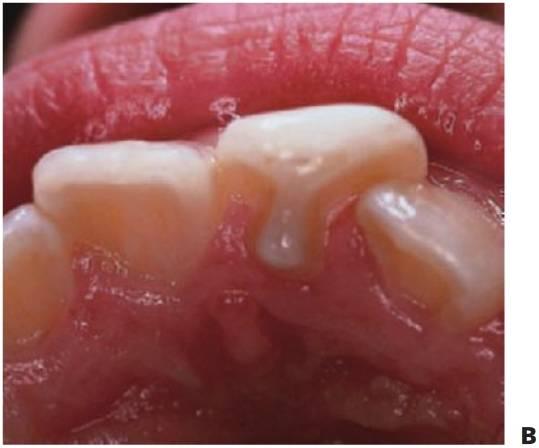

Displasias ectodérmicas

La displasia ectodérmica describe un grupo de trastornos del desarrollo que con frecuencia son heredados y afectan a las estructuras derivadas del ectodermo, como el pelo, los dien tes, las uñas, la piel y las glándulas sudoríparas. La forma más común es la forma hipohidrótica ligada al cromosoma X (OMIm305100, EDA1, Xq12-q13.1 [brazo corto del cromosoma X]). En este trastorno, la presentación usual es la de un niño varón con:

- Varios dientes ausentes (fig. 9.1 B).

- Cabello fino y ralo (fig. 9.2A, B).

- Piel seca (fig. 9.2A).

- Hipoplasia maxilar.

- Eversión de los labios.

- Pigmentación alrededor de la boca y los ojos.

Los dientes son pequeños y cónicos y a menudo presentan un gran diastema anterior (fig. 9.3). Sus manifestaciones pueden limitarse a un solo diente ausente o a un incisivo lateral en clavija (v. hipótesis de Lyon, más adelante) y las mujeres heterocigóticas suelen ser diagnosticadas gracias a este tipo de dentición.

Dentro del grupo de displasias ectodérmicas, se observan asimismo modos de herencia autosómica tanto dominante como recesiva. Si se compara con la displasia ectodérmica hipohidrótica ligada al cromosoma X, en las familias con este trastorno no existen diferencias tan acentuadas en cuanto al grado de trastorno entre los hombres y las mujeres (figs. 9.2A, 9.4). Se han identificado mutaciones en el gen MSX1 (4p16.1) en familias con terceros molares y segundos premolares ausentes con o sin paladar hendido/labio leporino, así como en familias con el síndrome diente-uña (Witkop). Se han observado mutaciones del gen PAX9 (14q12-q13) en otras familias con dientes ausentes de forma autosómica dominante.

Tratamiento

El objetivo del tratamiento es proporcionar una función adecuada, mantener la dimensión vertical y restaurar el aspecto estético. La mejor opción desde el punto de vista de las consideraciones sociales es el inicio del tratamiento a los 2-3 años de edad. Sucede a menudo que los padres pretendan con ahínco «normalizar» el aspecto del niño. Un primer paso suele ser la colocación de restauraciones de composite para enmascarar el aspecto «similar a un colmillo» del diente anterior caniniforme (fig. 9.3A). Más adelante se efectuará la provisión de prótesis para que sufra menos burlas, sobre todo en el momento en que el niño empieza a ir a la escuela. La prótesis puede prepararse tan pronto como al niño se le puedan tomar impresiones, pero la realidad es que el primer juego de prótesis suele llevarse en el bolsillo y a medida que el niño crece se desarrolla el deseo de tener un aspecto más normal. Gracias a una incentivación y refuerzo positivo del niño, la mayoría de los niños llevarán puestas sus prótesis.